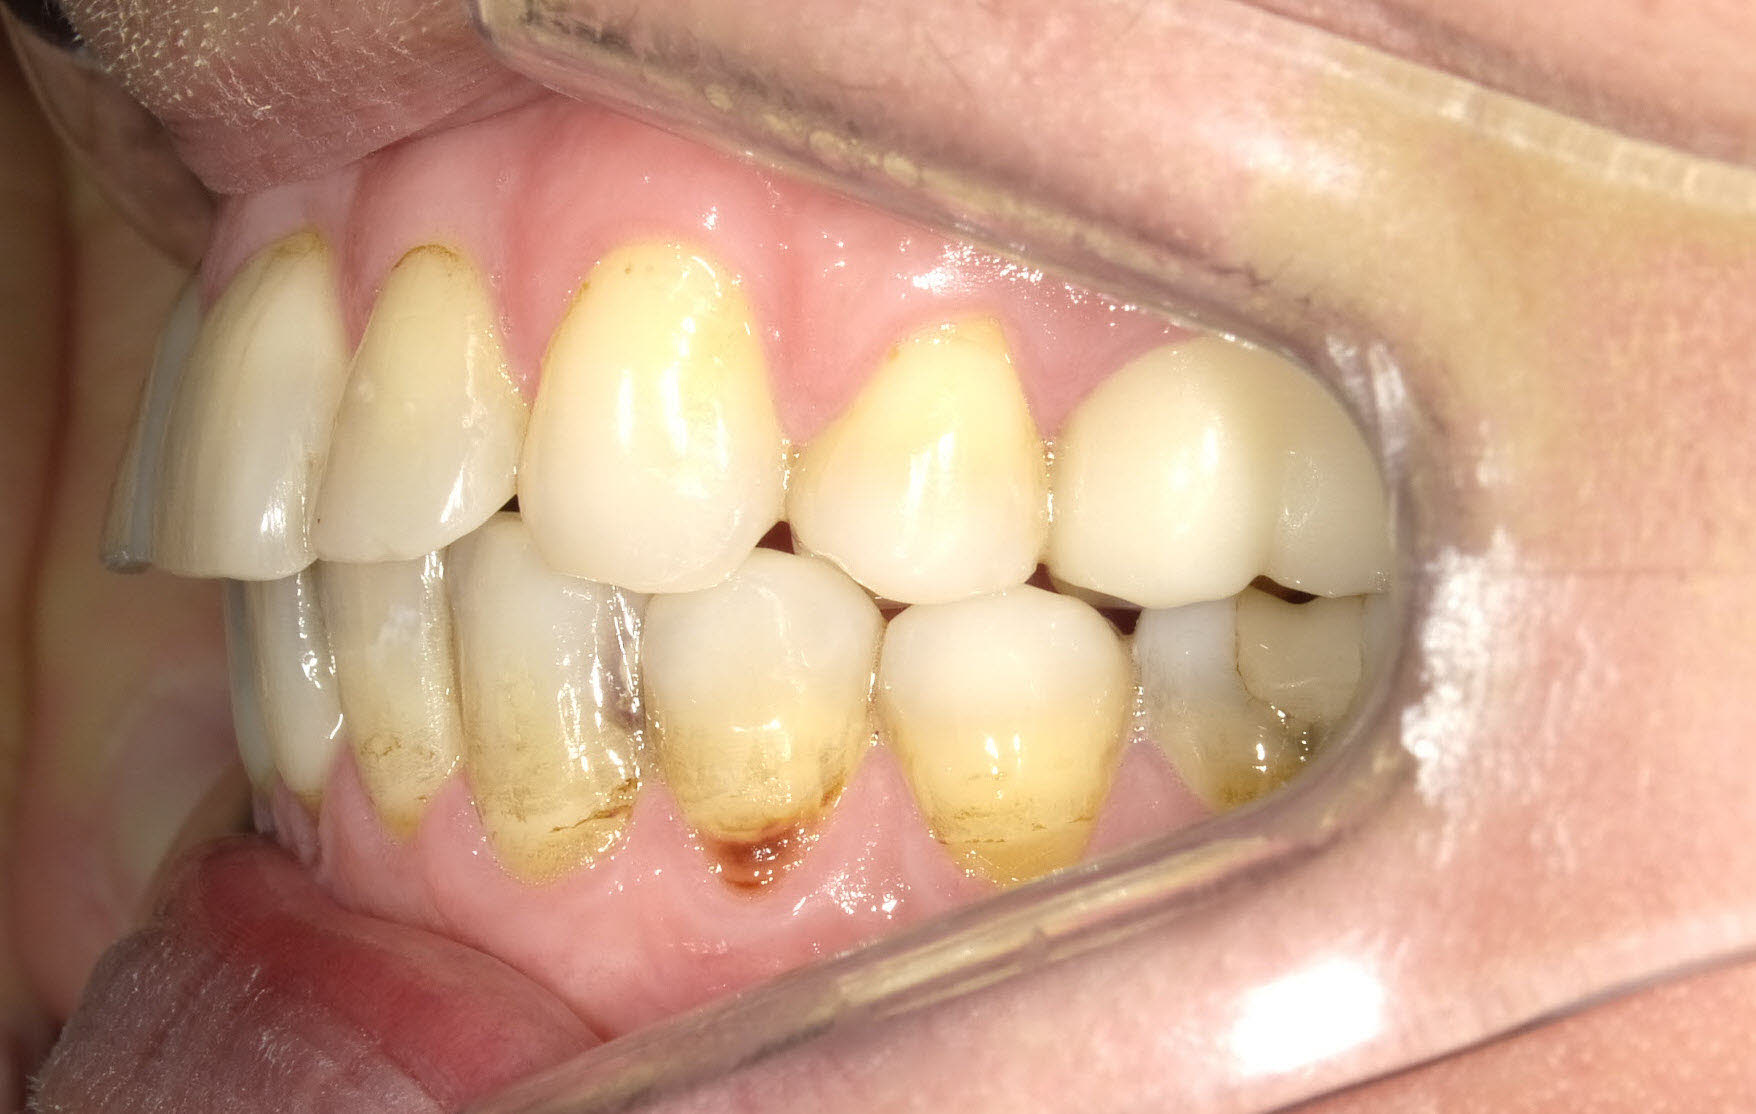

Während der Behandlung

Links Zustand beim Einsetzen der festen Zahnspange, rechts Situation unmittelbar nach der Operation (nach 2 Jahren, 4 Monaten). Der Unterkiefer wurde chirurgisch vorgesetzt und dadurch die Zahnreihen besser in Kontakt gebracht. Die Operation wurde an der Uniklinik Homburg durchgeführt. Eine Feineinstellung der Verzahnung ist aber im Laufe der kieferorthopädischen Nachbehandlung noch erforderlich.